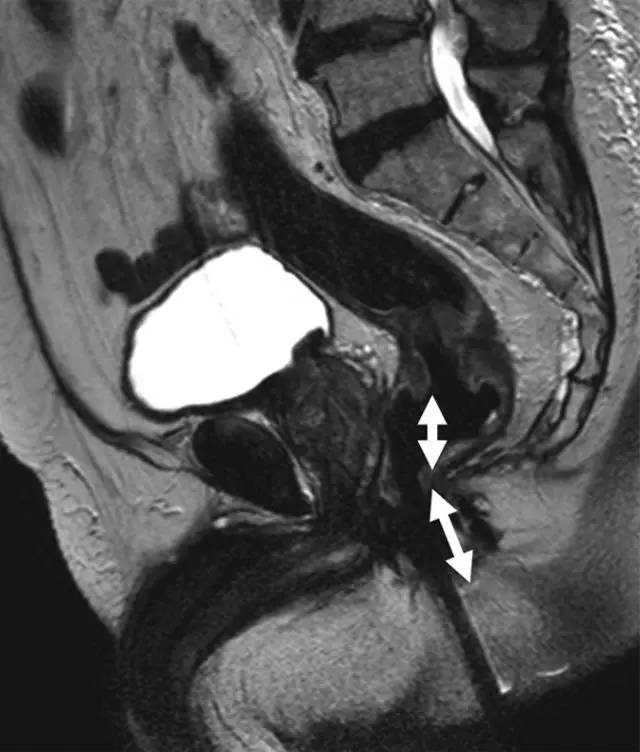

图 1 低位直肠癌患者的矢状 T2 加权图像。箭头显示肿瘤下缘距离肛缘 <5 cm。测量必须以相对直线的方式进行,以便与乙状结肠镜检查相符。